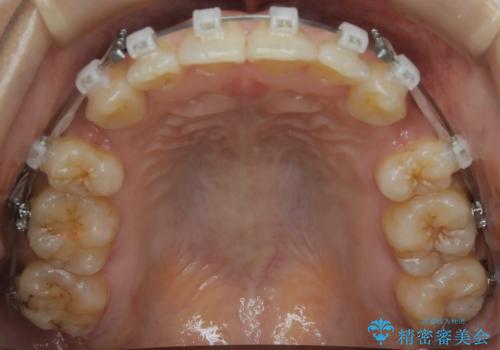

前歯を後ろに下げたい ワイヤー矯正(クリア装置)

- 矯正装置

- クリア装置

- 前歯を後ろへ下げることを主訴に来院された患者様です。

10代の時に非抜歯でワイヤー矯正をしていました。

口元の突出感の改善や歯の移動量などを考慮し、抜歯を伴うワイヤー矯正での治療を選択しました。

抜歯を行うことで前歯を後ろへ下げるスペースを獲得し、口元の突出感や歯のガタつきを改善していきました。